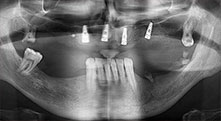

Implants

The four implants are in situ, as planned. The distal maxillary molars can still be used to fix the lined denture, which was introduced one month after implantation.